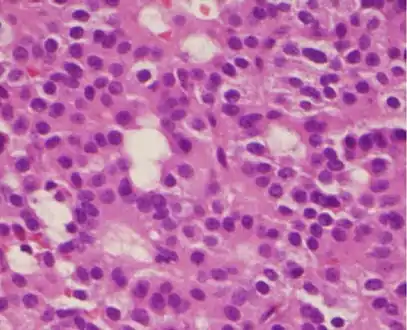

- Histological classification utilizes an immunohistological characterization of the tumors in terms of their hormone production.[47] Historically they were classed as either basophilic, acidophilic, or chromophobic on the basis of whether or not they took up the tinctorial stains hematoxylin and eosin. This classification has fallen into disuse, in favor of a classification based on what type of hormone is secreted by the tumor. Approximately 20-25% of adenomas do not secrete any readily identifiable active hormones ('non-functioning tumors') yet they are still sometimes referred to as 'chromophobic'.

_GH_production.jpg.webp) Somatotroph pituitary adenoma, showing acidophilic cytoplasm

Somatotroph pituitary adenoma, showing acidophilic cytoplasm A silent gonadotroph pituitary adenoma which is, in this case, is eosinophilic (contrary to normal, basophilic, gonadotroph cells)